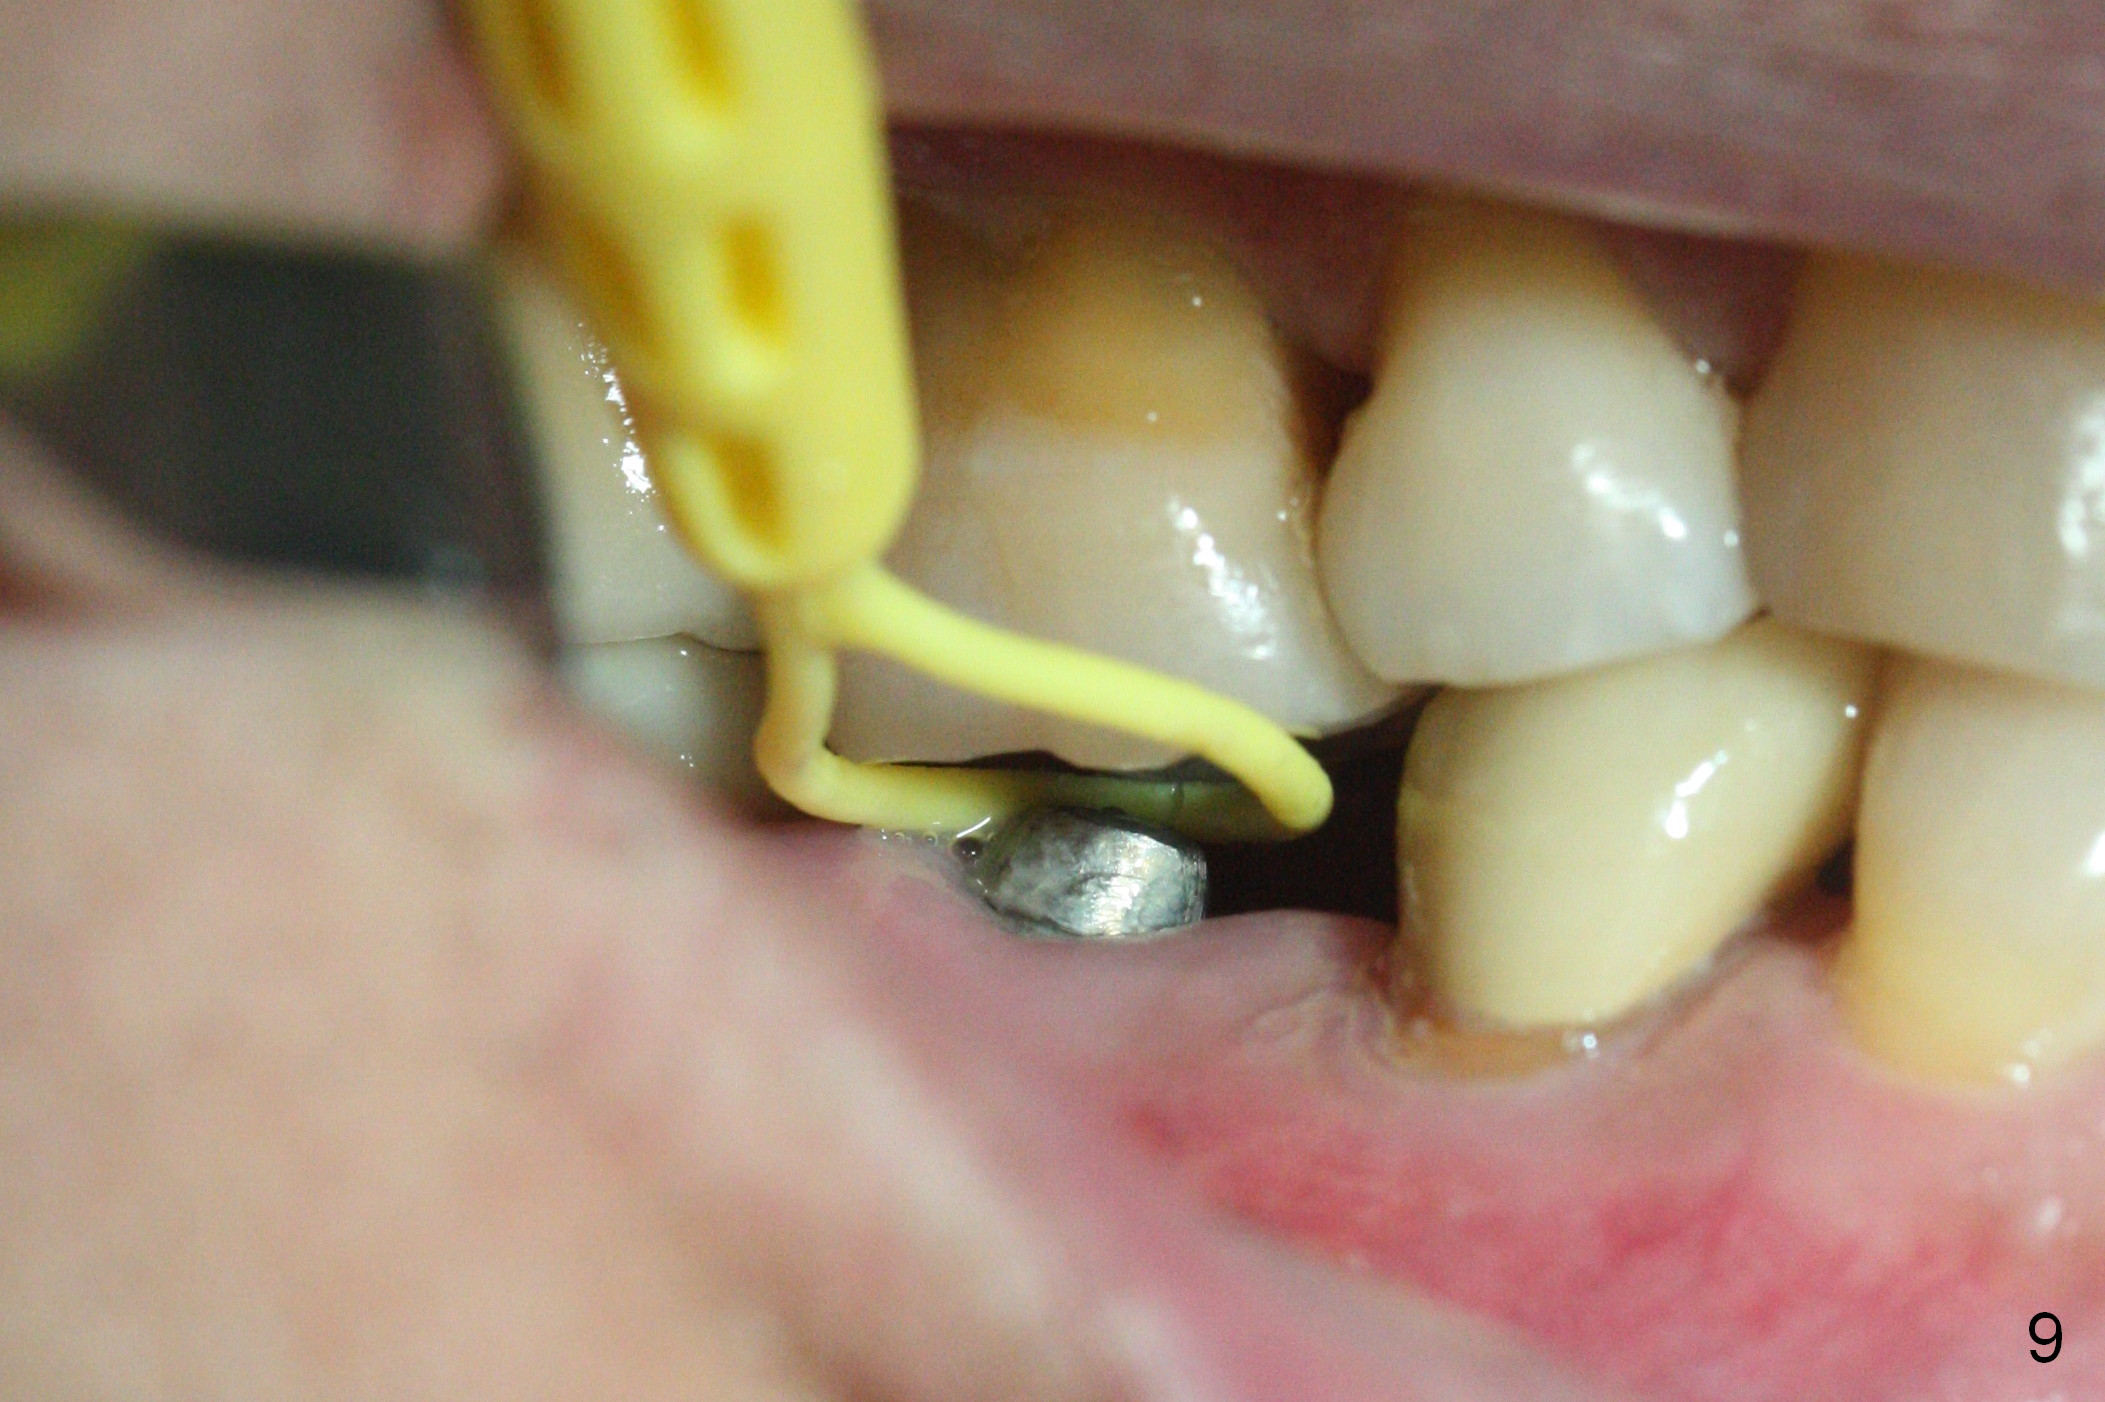

A 47-year-old man has history of bruxism, chipping porcelain from #29-31 FPD (Fig.1). Following sectioning the FPD, osteotomy is created (Fig.2: 5x14 mm drill) for placement of a 5x14 mm tissue-level implant (Fig.3,4). A 4x3 mm abutment (Fig.5 (lingual view) A) with 3 vertical slots (* for increased retention) is placed to retain periodontal dressing. The crown over the implant has dislodged 3 times over 28 months post cementation (Fig.6). It appears that the top of the abutment is too rounded. Clinical exam shows that the abutment height can be more, although the tooth #3 is supraerupted (Fig.7 (orthodontic intrusion is not indicated because of furca infection)).

Pre-impression photos show supraerupted #3 (Fig.7). Clearance is a little more than 1 mm between the mesiopalatal cusp of #3 (Fig.7 *) and the rounded abutment (Fig.8). Removal of the abutment turns out to be easy. Reduction is confined to the opposing tooth (slopes of the cusps). No occlusal reduction is done for the new abutment as mentioned above except for 2 retention grooves. One-mm reduction ring barely passes the occlusal clearance (Fig.9). No cement is applied to the abutment in case a longer abutment may be required. Bone density seems to remain the same or increase after cementation of a new crown (Fig.7). The redo crown remains in place 1 year post cementation.